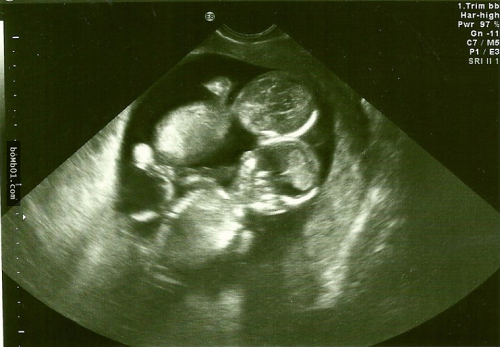

| Kết quả siêu âm cho thấy Kate mang thai đôi |

Theo đó, bác sĩ cho biết, thai nhi bị mắc hội chứng Monoamniotic. Đây là hội chứng xảy ra khi hai bào thai chia sẻ chung một túi ối không màng ngăn khiến dây rốn quấn quanh thai nhi trong quá trình phát triển.

Điều này sẽ dẫn đến tình trạng thai thiếu oxy và chết lưu trong bụng mẹ. Xác xuất xảy ra hội chứng Monoamniotic này là 1% và tỷ lệ sống sót chỉ đạt 50%.